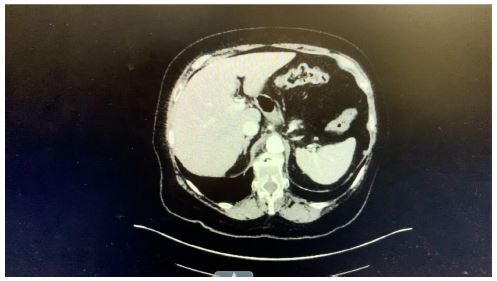

On June 27, 2024, a CT scan of the abdomen was performed, revealing significant findings. The report described ‘‘biliary ductal obstruction at the ampulla with severe biliary ductal dilatation.’’ Specifically, the common bile duct was measured at 1.6 cm in diameter, and the common hepatic duct was 2.3 cm, indicating a notable obstruction. Additionally, the scan noted ‘‘fluid and adjacent duodenal sweep but no soft tissue mass.’’

Figure 1: CT scan of the abdomen.

The patient’s initial presentation, including symptoms of sepsis and elevated inflammatory markers, was complicated by the rare finding of congenital gallbladder agenesis. The imaging findings from the CT scan and HIDA scan, along with the ERCP results and surgical exploration, collectively confirmed the diagnosis. The CT scan showed biliary ductal obstruction and dilation, while the HIDA scan’s nonvisualization of the gallbladder and the ERCP’s findings of a tubular structure without a gallbladder were consistent with the congenital aplasia. Given the patient has a clinical and paraclinical picture of obstructive jaundice with acute cholangitis, the team decided to conduct an ERCP and circumvent the use of an MRCP to further aid in diagnosis and therapy.